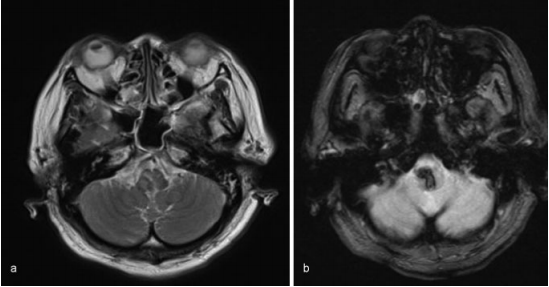

入院后,她出现白天呼吸抑制(每分钟呼吸10次)和夜间呼吸暂停。然后她进行插管,并用呼吸机控制呼吸。MRI未发现明显的出血原因,如海绵状畸形、动静脉畸形或肿瘤。患者随后被诊断为高血压原发性延髓出血,随后通过持续静脉输入钙通道阻滞剂来降低血压。然而,病人的呼吸抑制没有改善。

图:磁共振图像显示出血没有明显的病理原因,(a)T2加权(b)T2加权。